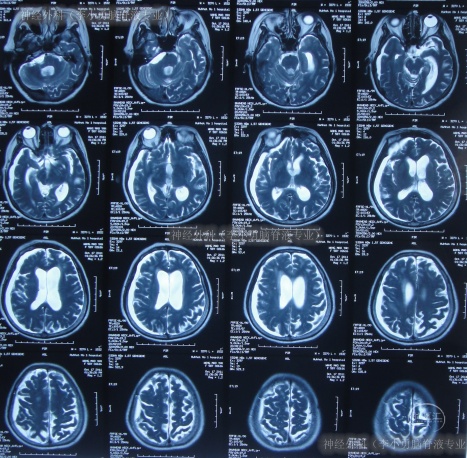

第2家医院出院1月余即2012年2月7日,夜里起夜突然又重复发作以前的症状(恶心呕吐、头昏),且比前2次发作严重,2012年2月8日住入第3家医院:呼和浩特市某三甲医院的神经外科治疗,入院查头颅CT(图-2)和MRI(图-3);脊髓核磁(图-4);肺部CT(图-5)及多次腰椎穿刺脑脊液化验检查(糖低、蛋白高),诊断为:结核性脑膜炎,脑积水。

图-2:2012年2月9日头颅CT

图-3:2012年2月9日头颅核磁